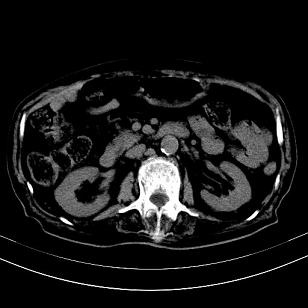

标题: CT19407:肝内还是肝外原发性肿瘤??

男,63岁,高血压病史40余年,

来源-右侧肾上腺。

考虑右侧肾上腺巨大占位;恶性?

肝内多发低密度找;转移瘤?

另:右肾结识,多发小囊肿。

考虑右肝后叶肝癌(部分外生)伴肝内多发性转移;右侧肾上腺区恶性肿瘤并肝转移待排。

考虑右侧肾上腺肿瘤并肝内多发转移。右侧肾上腺呈“八”字形,包括内侧枝及外侧枝,内侧枝受压,考虑外侧枝原发肿瘤。”

考虑肝右后叶肝癌(部分外生)伴肝内多发性转移;不排除右侧肾上腺区恶性嗜铬细胞瘤并肝转移。